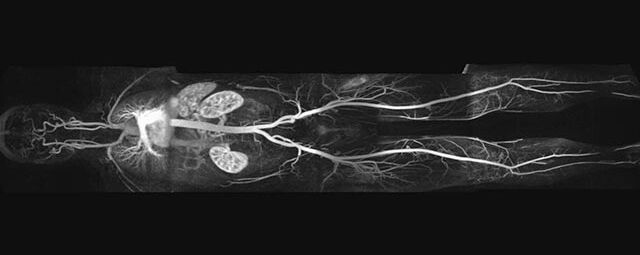

MR-Angiografie (MRA)

• MR-Angiographie mit Kontrastmittel

• Erfassung arterieller und venöser Gefäße/Bypässe aller Körperregionen mit 3D-Rekonstruktion

• Bauchgefäße

• Erfassung und Verlaufskontrolle bei arteriellen Aneurysmen (Aussackungen der Arterien), vor allem der Bauchaorta

• Darstellung von Gefäßengen an Nierenarterien, Baucharterien und Becken-/Beinarterien